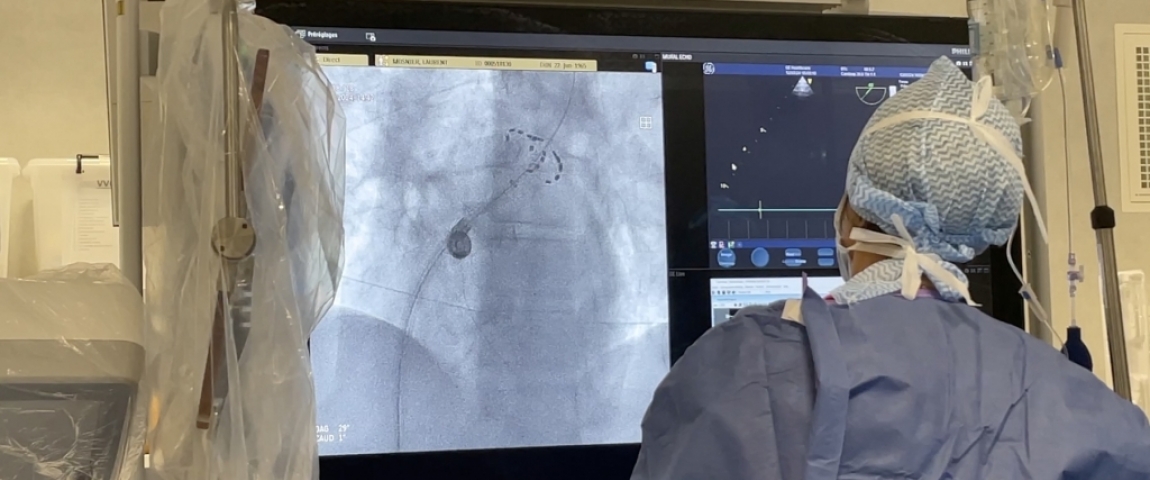

Dotée de technologies de pointe, la nouvelle salle de rythmologie permet de traiter de manière plus efficace et plus rapide les patients atteints de troubles cardiaques.

Ces nouvelles technologies existent déjà dans l'Hexagone mais le CHU de Saint-Etienne est l'un des premiers à y avoir accès dans la région Auvergne-Rhône-Alpes.

Le CHU utilise notamment une nouvelle source d'énergie : l'électroporation. Ce système élimine les foyers anormaux de manière plus sécurisée.

"C'est une énergie qui est beaucoup plus sûre que les énergies utilisées précédemment. Elle permet une plus grande sécurité dans le traitement du trouble du rythme cardiaque" indique le Professeur Da Costa, médecin cardiologue au CHU de Saint-Etienne.

Le CHU a investi 1,8 million d'euros dans cette nouvelle salle. Plusieurs patients ont déjà pu en profiter ces derniers mois.